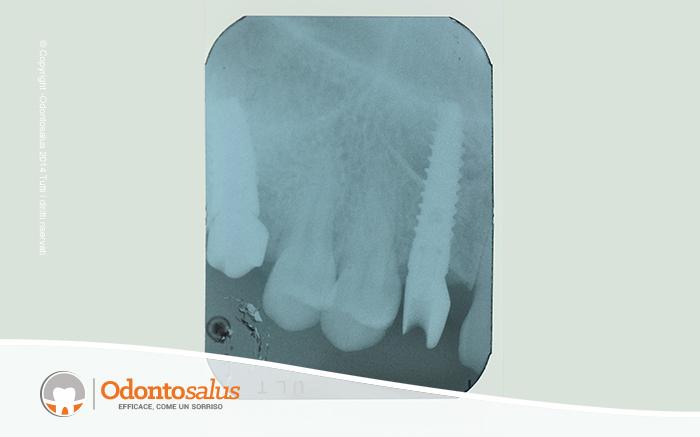

Inizialmente è stato effettutao un trattamento ortodontico per riportare l’elemento incluso in arcata. Tuttavia, come a volte accade in relazione all’età del paziente, alla densità ossea o alla posizione del dente incluso, ortodonticamente non è stato possibile riallineare il canino con gli altri denti. Si è proceduto, pertanto, con l’incisione del lembo, la scopertura e l’estrazione del canino, il riempimento del deficit osseo creato, l’applicazione dell’impianto e, data la sua stabilità, l’inserimento del provvisorio nella stessa seduta.

A distanza di circa tre mesi è stato inserito l’elemento definitivo, per un ottimo risultato sia funzionale, salvaguardando la gengiva e l’osso, che estetico.